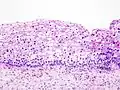

Die CIN wird in drei Schweregrade eingeteilt:

- CIN I: (leichte Dysplasie) geht von basal aus bis höchstens einem Drittel der Höhe des Epithels;

- CIN II: (mittelgradige Dysplasie) bis zu zwei Drittel des Epithels;

- CIN III: (hochgradige Dysplasie) durchzieht fast das gesamte Epithel (Carcinoma in situ).

Normales zervikales Epithel. -

Grad I CIN. -

Grad II CIN. -

Grad III CIN.